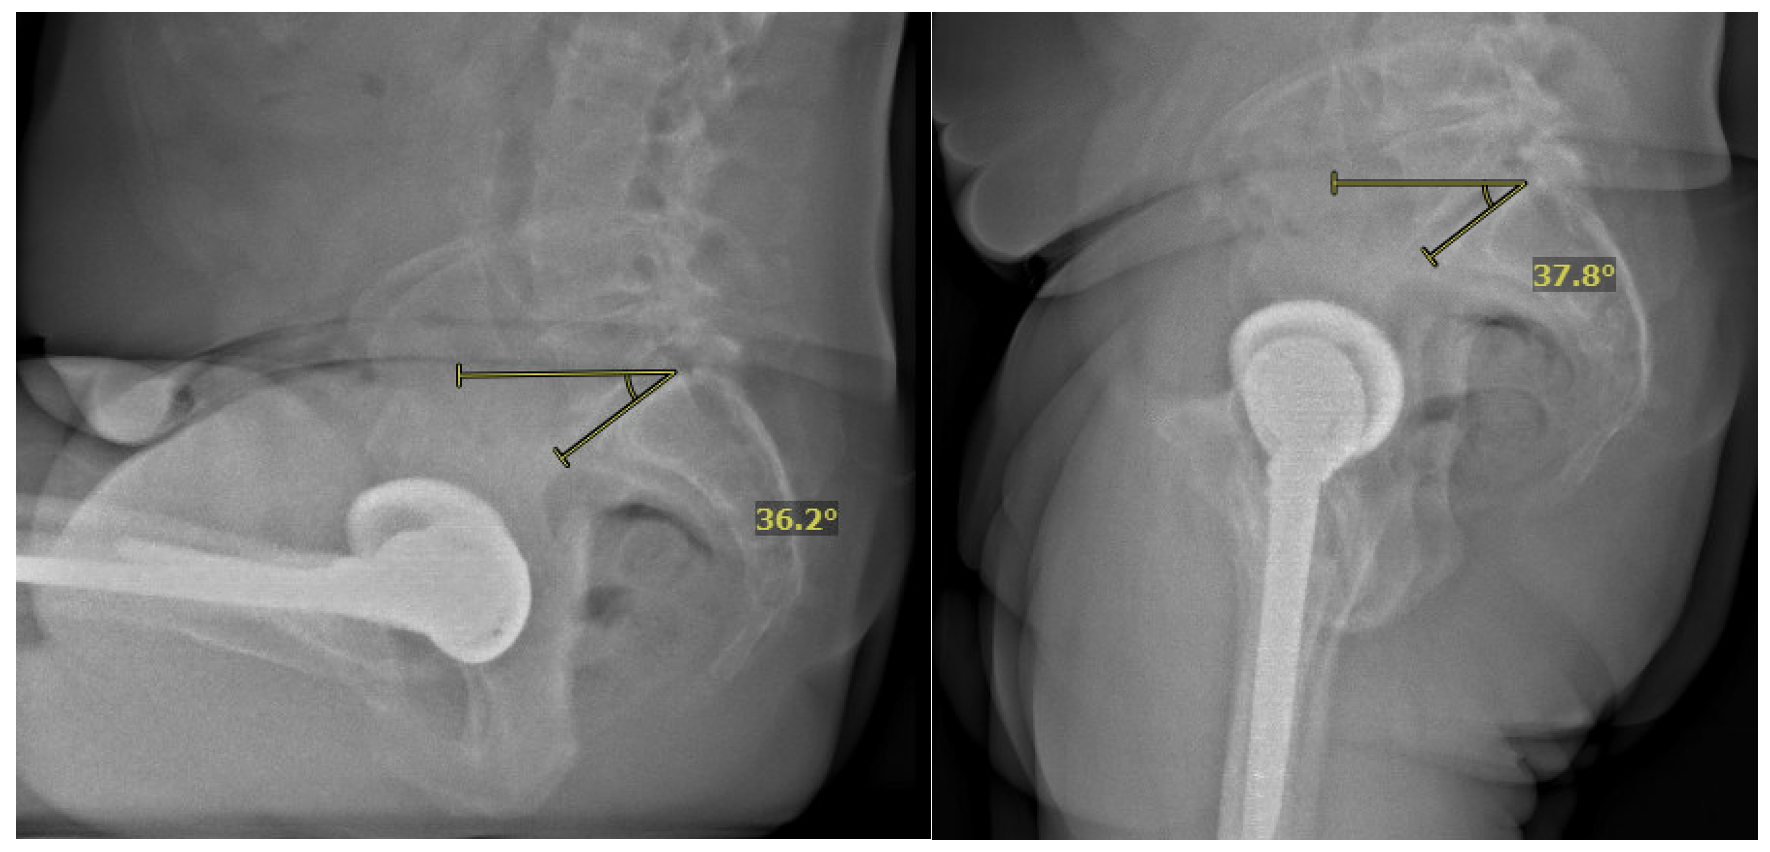

Left Hip Instability. In 2024, approximately 23 years after his index surgery, the patient began experiencing recurrent dislocations of his left hip. Evaluation included a sit-to-stand EOS scan, which revealed that his spine had become extremely stiff in a “stuck standing” position (Figure 2). This spinopelvic imbalance was identified as a significant contributing factor to the instability, as the restricted spinal motion produced unfavorable changes in pelvic tilt and, consequently, the functional orientation of the acetabular component during postural transitions.14

Further advances in THA stability have stemmed from an increased understanding of the lower lumbar spine dynamics on hip mobility. Stiff spine, defined as a change in sacral slope of less than 10 degrees between sitting and standing positions. “Stuck-standing” is defined as a sacral slope measurement greater than 30 degrees in both sitting and standing lumbar spine films, with a difference of less than 10 degrees. Alternatively, “Stuck-sitting” has been defined as a sacral slope measurement of less than 30 degrees in both sitting and standing lumbar spine films, with a difference of less than 10 degrees. These insights have provided new cup implant target zones to ensure hip stability.

- In 2024, 23 years later, he developed recurrent dislocations; sit-to-stand EOS imaging identified spinopelvic stiffness as a key contributor of instability, with a “stuck standing” pattern.

Advanced Planning in Revision Surgery. This case also demonstrates the value of modern preoperative and intraoperative planning tools in revision arthroplasty. Sit-to-stand EOS imaging identified the patient’s spinopelvic stiffness as a critical driver of instability, revealing a “stuck standing” pattern in which limited spinal flexion-extension resulted in inadequate posterior pelvic tilt during standing, effectively reducing functional acetabular anteversion.18